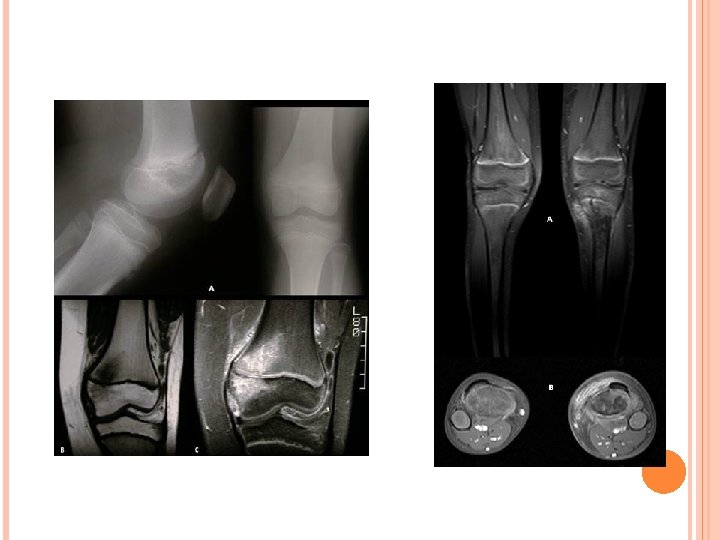

DIAGNÓSTICO EXAMES DE IMAGEM Radiografia simples Realizado em todos os pacientes Método tardio Excluir outras diagnósticos Alterações: >7 dias dos sintomas – elevação periosteal, espessamento cortical 10 -21 dias – destruição ossea

1 semana de sintomas

DIAGNÓSTICO EXAMES DE IMAGEM RNM Alta sensibilidades (97%) e especificidade (92%) Delinear a localização e extensão do comprometimento osseo Envolvimento da placa de crescimento

DIAGNÓSTICO Exames de imagem Radiografia Alargamento do espaço articular Ao analisar as radiografias, é útil comparar a extremidade envolvida com o lado oposto USG Derrames articulares

DIAGNÓSTICO Exames de imagem Cintilografia Diagnostico precoce Suspeita de osteomielie RNM Mais sensível para derrame articular Avalia possível osteomielite ou abscesso se não há resposta em 48 horas de ATB